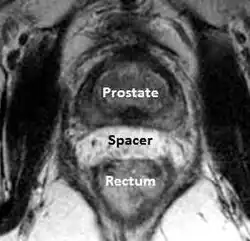

Prostata-Rektum-Hydrogel-Abstandshalter

Bei Prostatakrebs ist eine Strahlentherapie, die entweder in Form einer Brachytherapie oder externen Strahlentherapie durchgeführt wird, eine der am häufigsten gewählten Behandlungsmethoden.

Obwohl die Strahlentherapie bei Prostatakrebserkrankungen im Vergleich zu anderen Behandlungsmethoden bessere Erfolge zeigt, birgt die Verletzung des Rektums durch die Bestrahlung (strahleninduzierte Proktitis) eine Gefahr, da sich das Rektum unmittelbar hinter der Prostata befindet. Die durch Strahlen ausgelöste Schädigung des Rektums kann zu Durchfall, rektalem Druck, zur Schleimhautproduktion und zu Blutungen führen. Bis zum Auftreten dieser Symptome kann es sechs bis zwölf Monate dauern. Die Symptome können jedoch zu jedem Zeitpunkt bis zu 30 Jahren nach der Bestrahlungstherapie auftreten.[101][102]

Eine aufkommende Strategie zur Minderung dieser rektalen Schädigung ist die Platzierung eines Abstandshalters zwischen diesen beiden Strukturen, wodurch das Rektum auf wirkungsvolle Art und Weise vom hochdosierten Strahlenfeld weggedrückt wird. Forschern war es möglich, diese Abstandshalter herzustellen, indem sie verschiedene Materialien in dem potenziellen Raum zwischen der Prostata und dem Rektum platzierten.

Die Injektion von Hyaluronsäure in den Raum zwischen Prostata und Rektum führte zu einem zusätzlichen Raum von mehr als einem Zentimeter ohne Beschwerden durch Tenesmen oder das Gefühl einer rektalen Füllung. Bei Patienten, die mit Hyaluronsäure behandelt wurden, traten im Vergleich zu Patienten, die keinen Abstandshalter aus Hyaluronsäure erhalten hatten, bei proktoskopischen Untersuchungen deutlich seltener rektale Schleimhautbeschädigungen (5 % vs. 36 %, p = 0,002) und keine makroskopischen rektalen Blutungen (0 % vs. 12 %, p = 0,047) auf.[103] Eine ähnliche Studie wurde mittels Collageninjektionen in den gleichen Raum durchgeführt. Mit dieser Methode schuf man einen Raum von durchschnittlich 1,1 cm zwischen der Prostata und dem anterioren Rektum, was zu einer mehr als 50-prozentigen Minderung der rektalen Strahlungsdosis während der Strahlentherapie an der Prostata führte.[104]

Forscher bewerteten einen absorbierbaren Ballon, der in den Raum zwischen Prostata und Rektum eingesetzt wurde, und ermittelten einen beinahe zwei Zentimeter großen Raum mit einer errechneten Reduktion der rektalen Bestrahlung.[105] Untersuchungen von in gleichem Raum injiziertem, absorbierbarem Hydrogel (das sich derzeit in den USA in der Phase der klinischen Erprobung befindet), resultierten in einem zusätzlichen Raum von einem Zentimeter mit einer Minderung der rektalen Strahlung (V70) von 60 %.[106][107]

Obwohl sich die Prostata-Rektum-Abstandshalter noch in der Phase der klinischen Erprobung befinden, besteht ein vielversprechendes Potenzial dahingehend, dass sie nicht nur zur Minderung unbeabsichtigter rektaler Strahlenaussetzung und der daraus resultierenden Komplikationen beitragen, sondern außerdem höhere Dosierungen bei der Strahlentherapie von Krebspatienten ermöglichen. Somit kann die Überlebensrate der Patienten verbessert werden.[108] Zusätzlich kann durch eine höhere Dosierung pro Behandlung eine vollständige Behandlung mit weniger Arztbesuchen realisiert werden, was zum einen angenehmer für den Patienten ist und zum anderen zu erheblichen Einsparungen der medizinischen Kosten führt.[109]

Im Gegensatz zu den USA, in denen sich das Hydrogel noch in der klinischen Erprobung befindet, ist das Hydrogel in Europa bereits CE-zertifiziert und in einigen Ländern auf dem Markt erhältlich.